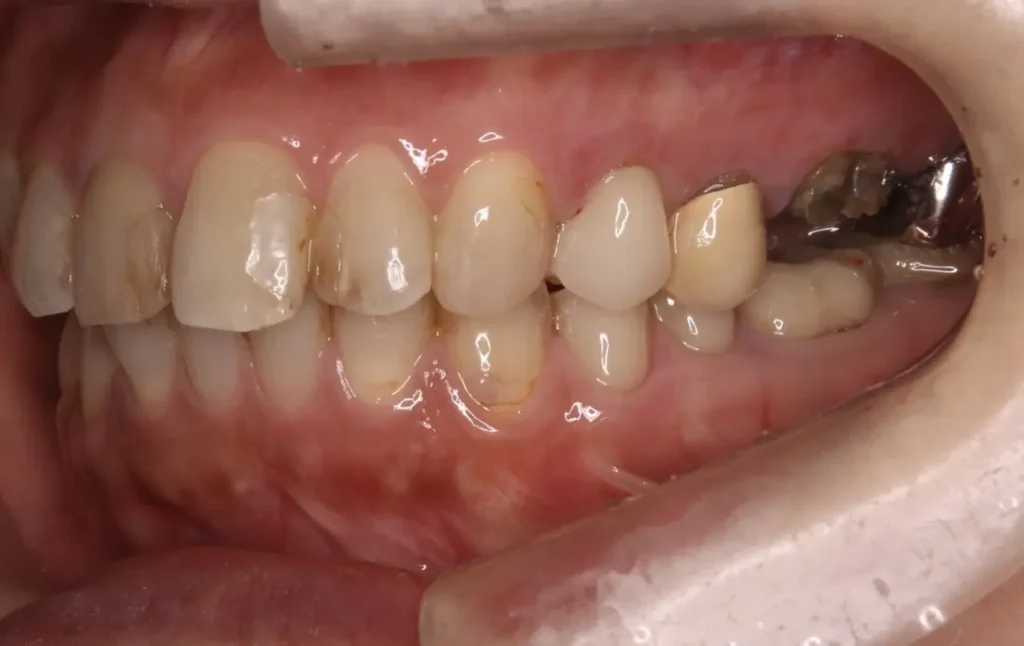

自費根管治療症例2 治療前

左下の奥歯が根の治療を受けているが治らない。

初診時

管の分かれている部分に根の治療による穿孔がありました